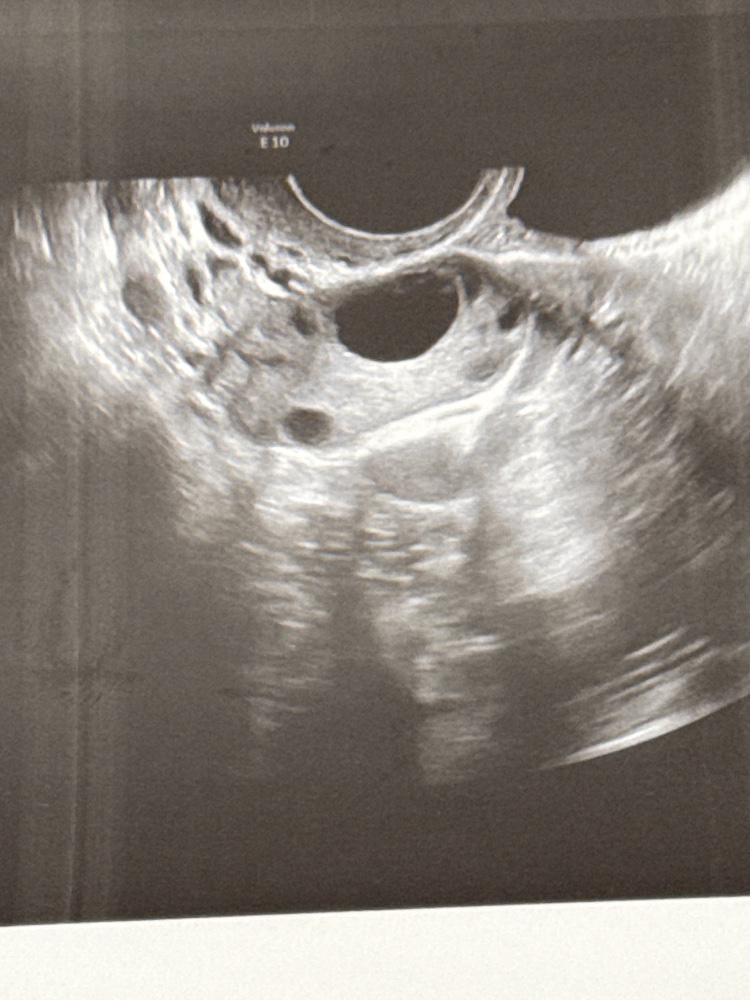

Обычный цикл составляет 30 дней. Этот цикл ановуляторный, ходила на фолликулометрию с 6 по 16ДЦ.

сейчас на 28ДЦ обнаружен ДФ 14мм. Как думаете возможна ли овуляция